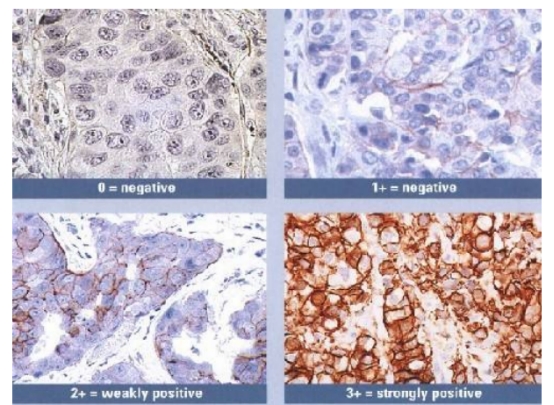

Typical example: Staining of paraffin-embedded human breast cancer tissue sections with different HER2 antibodies:

Left panel: Strong membranous positivity in cancer cells;

Right panel: Weak membranous positivity in cancer cells, indicating insufficient staining intensity of the antibody.

Common problem: Insufficient staining intensity can result in weak positivity in detection results.

Recommendation for Resolution: Appropriately adjust the antibody dilution ratio, or select antibodies with high staining intensity and high affinity.

HER-2 staining results vary among different breast cancer samples.